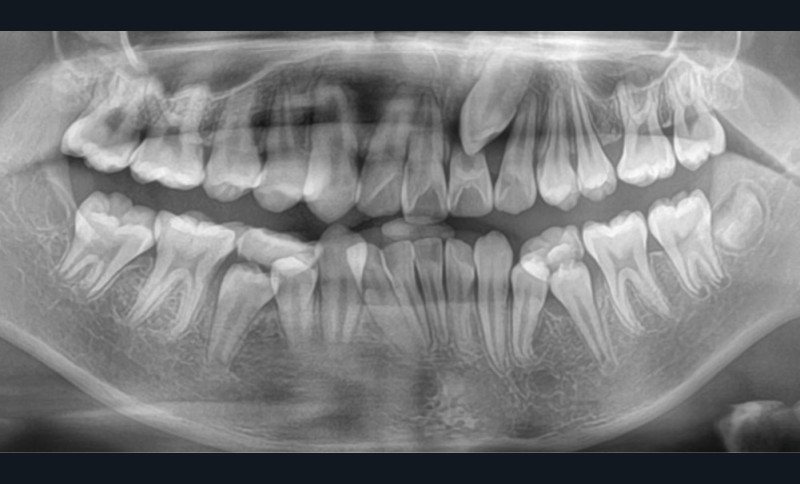

Une patiente âgée de 12 ans se présente en consultation, motivée par la position de son incisive centrale maxillaire, décrite comme « en avant », marquée par une dyschromie et une mobilité de grade 2 selon Muhlemann. L’examen clinique montre l’absence de 23 sur l’arcade, une dysharmonie dents-arcade marquée, un surplomb accentué, et une déviation des milieux inter-incisifs, conséquence du comblement spontané de l’espace de 23. L’ensemble s’inscrit dans un contexte de Classe I d’Angle molaire. L’orthopantomogramme révèle l’inclusion de 23, associée à une résorption radiculaire étendue aux deux tiers de 21. La 22 ne présente aucune altération visible.

La patiente, de profil normodivergent, présente une Classe I squelettique sans troubles fonctionnels (fig. 1-8).